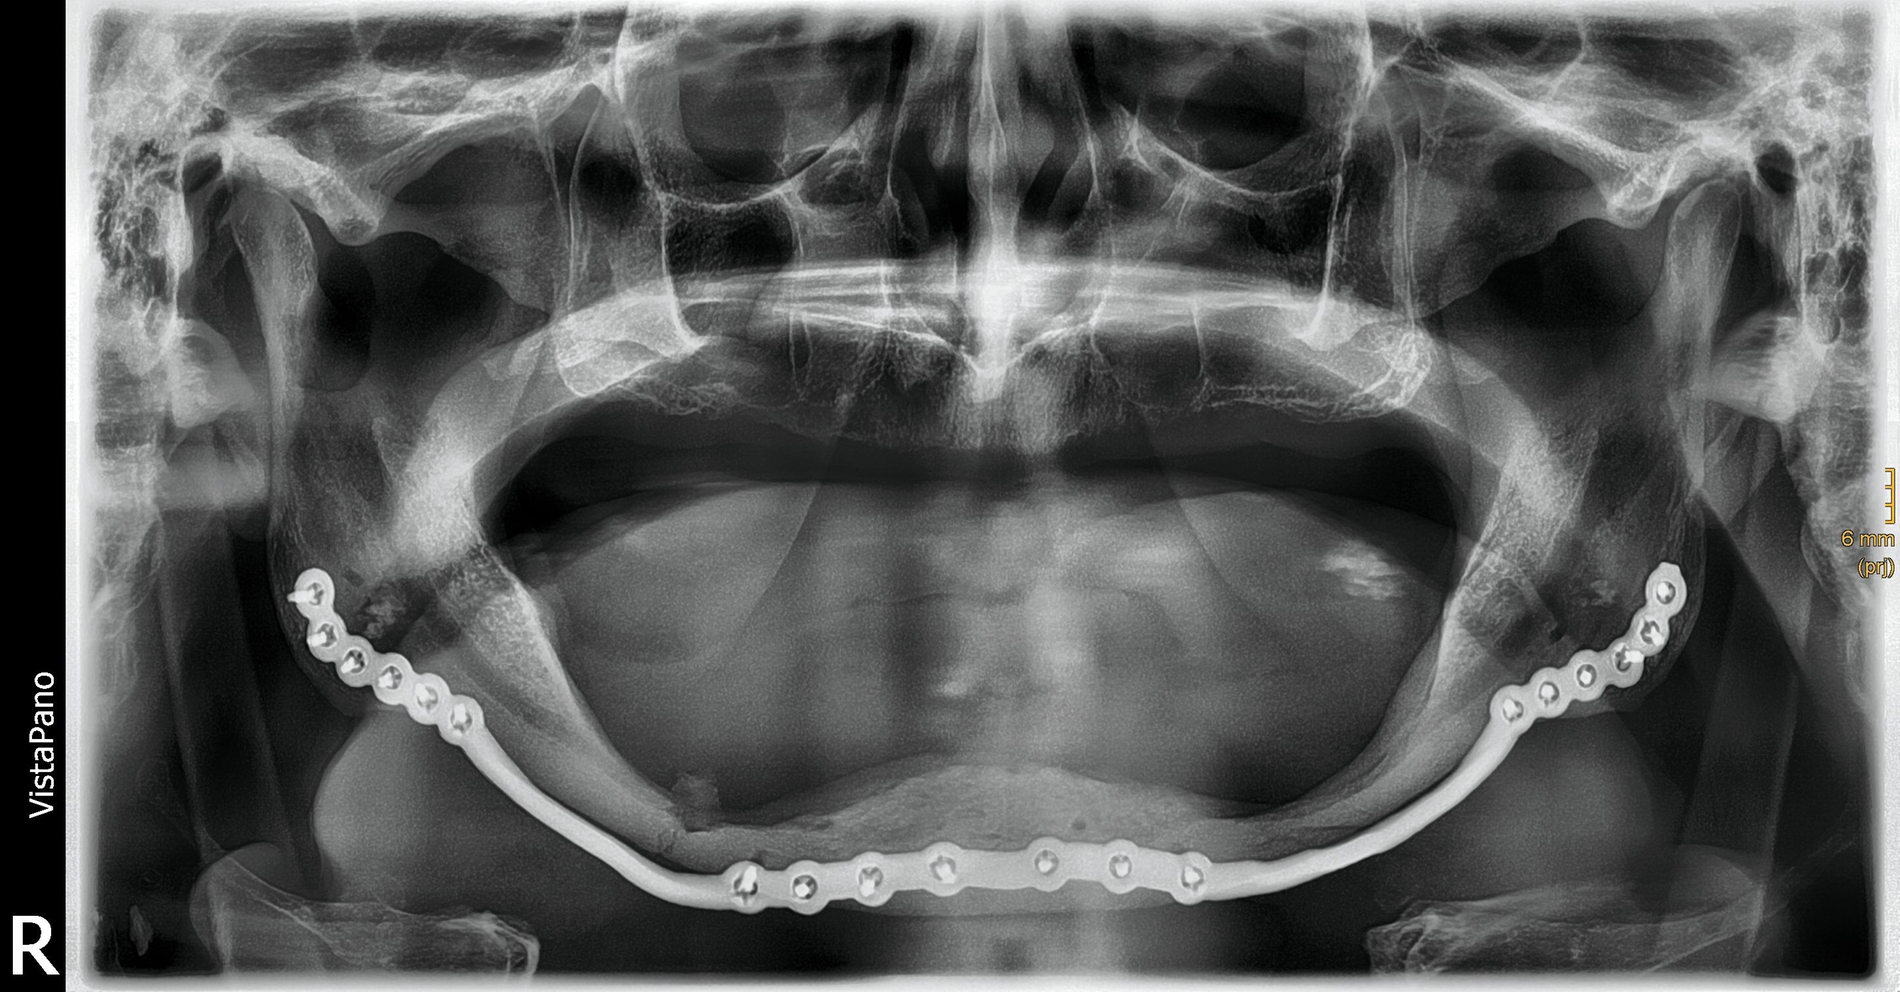

Bei zahnlosem Ober- und Unterkiefer erfolgte die virtuelle Repositionierung des frakturierten Unterkiefers (Abbildung 2a). Mittels CAD/CAM-Verfahren wurde eine stabile Rekonstruktionsplatte aus Titan (patientenspezifisches Implantat; PSI) geplant und hergestellt. Dabei sollte die Position des PSIs im Bereich des Unterkieferkorpus weit kaudal an der Basis sein, so dass später bei der Anpassung einer neuen Unterkieferprothese keine Interferenzen auftreten (Abbildung 2b).

Gleichzeitig konnte durch eine optimierte Bohrlochposition der Nervus alveolaris inferior geschont werden, eine Neurolyse brauchte nicht geplant zu werden. Außerdem wurden an die Zielreposition angepasste Bohrschablonen (drilling guides) hergestellt, die ein Vorbohren der späteren Schraubenlöcher in der exakten Zielposition ermöglichen (Abbildung 2c). In Kombination mit dem PSI sollte so eine Auto-Reposition des Unterkiefers durch die vorgegebenen Bohrlöcher erfolgen.

Operativ verwendeten wir einen beidseitigen extraoralen Zugang. Intraoperativ ließen sich die drilling guides exakt einbringen und wurden durch Schrauben fixiert. Nach Bohrung der vorgegebenen Bohrlöcher und Anbringen des PSIs konnte die Fraktur anatomisch reponiert und stabilisiert werden. Der postoperative Verlauf gestaltete sich komplikationslos, so dass der Patient am vierten postoperativen Tag nach Hause entlassen werden konnte. Vier Wochen nach der Operation zeigte sich in der klinischen Kontrolle ein reizfreier Situs mit guter Wundheilung.